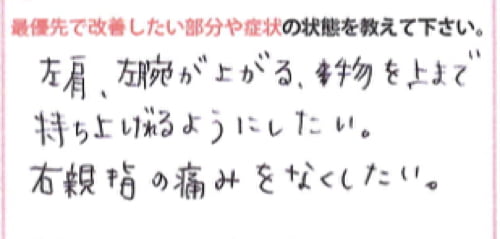

左肩・左腕が上がる、物を上まで持ち上げれるようにしたい。

とのご希望でした。

そして右手の親指はこの辺りに痛みがあるそうです。